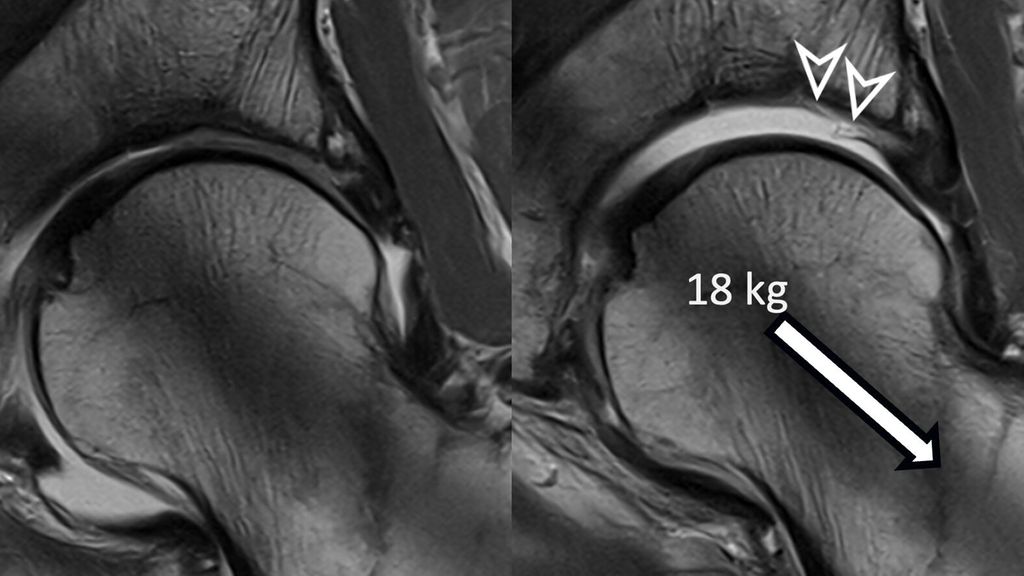

Fig. 1: Traction MR arthrography allows for better visualization of the opposing acetabular and

The hip is a ball-and-socket joint with the labrum dividing it into peripheral and central compartments. In standard MR arthrography, a contrast agent expands the hip capsule and flows into the central joint cavity through the acetabular notch. However, most of the contrast does not spread centrally due to the opposing femoral and acetabular cartilage layers, which typically prevent its accumulation unless there is significant cartilage damage. Therefore, visualizing acetabular cartilage delamination which represents a typical and frequent finding in patients with cam-type FAI is challenging with direct MR arthrography.4

To improve visualization of the central joint cavity during MR arthrography, axial leg traction can be applied, similar to the joint distraction needed during hip arthroscopy (Fig. 1). Traction MR arthrography of the hip has shown high accuracy in detecting chondrolabral lesions, ligamentum teres injuries, and intra-articular loose bodies and has demonstrated its value in predicting failure of FAI surgery.5–8 It is particularly helpful for better visualizing the extent of cartilage damage in older patients with mild radiographic joint degeneration and thus aid in surgical decision making. Traction MR arthrography can also detect unstable labral tears in patients with hip dysplasia and may aid in planning treatment for femoral head necrosis in young patients with early collapse and preserved joint space.4